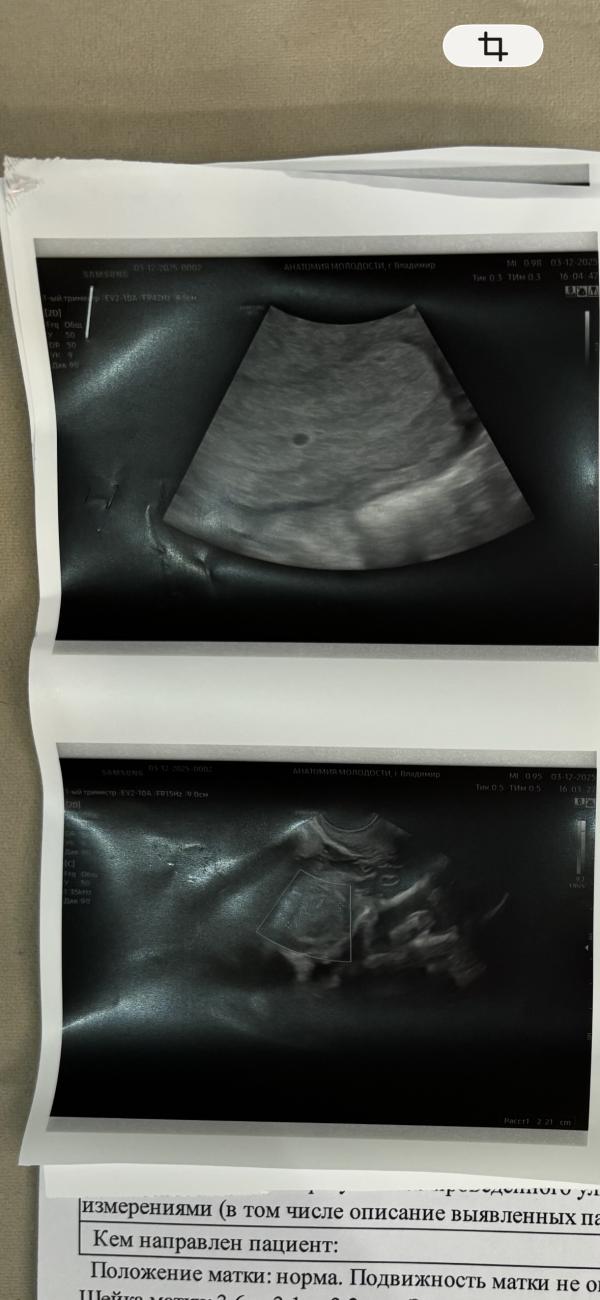

Сегодня была на узи

На узи увидела долгожданную горошинку